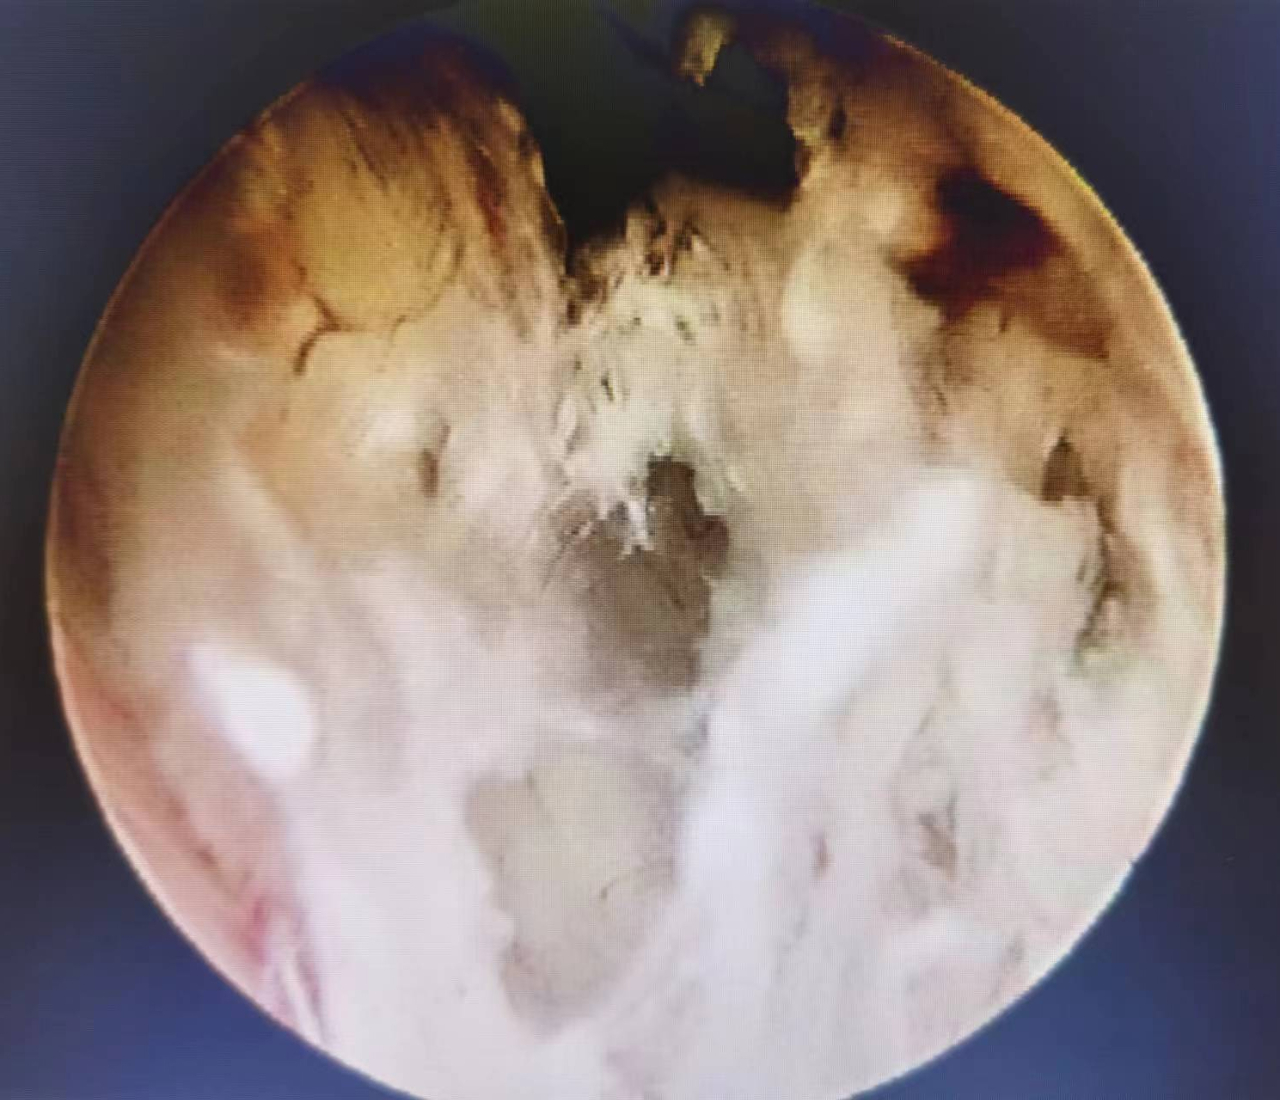

内膜增厚伴增生小血管

术后病理回报,为子宫内膜样腺癌。由于发现及时,李女士得到了及时治疗。